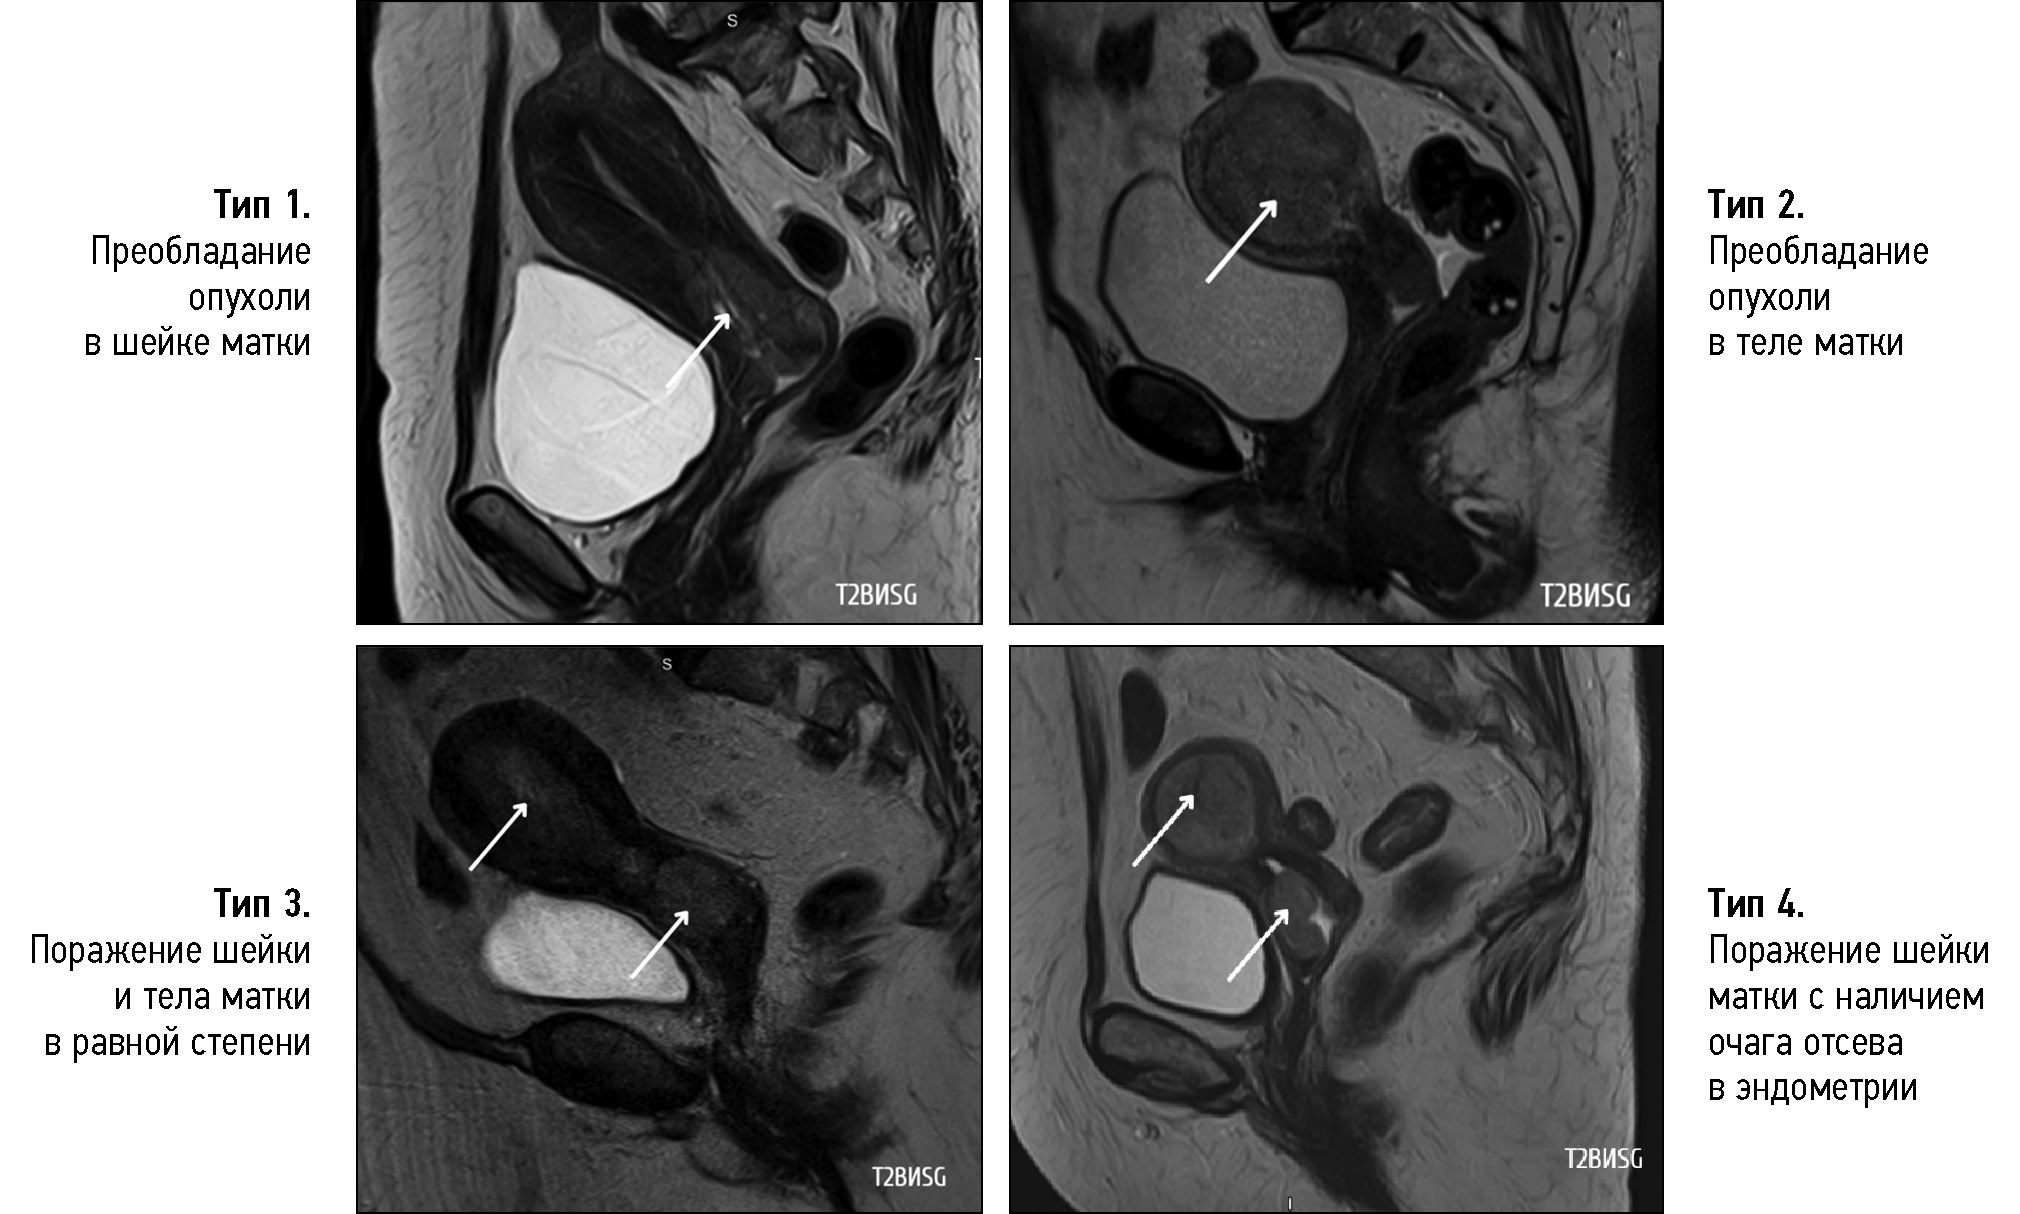

Differential diagnosis of the location of the primary tumor (whether the observed uterine abnormalities were endometrial carcinoma with cervical involvement or cervical carcinoma with endometrial involvement) was critical in the diagnostic search of gynecologists and radiologists for detecting uterine adenocarcinoma. All diagnostic controversies with predominant involvement in the uterine cavity were further reviewed by pathologists, and in all patients, endocervical adenocarcinoma (tumor of the cervix) was confirmed. Therefore, four types of tumor macrostructure were retrospectively classified based on the predominant location of the tumor according to MRI and pathology data (Fig. 4):

- Predominance of tumor in the cervix (n = 13; 65%)

- Predominance of tumor in the uterine body (n = 2; 10%)

- Equal involvement of endocervix and endometrium (n = 2; 10%)

- Isolated cervical lesion with CA lesion seeding into the uterine cavity (in the endometrium), confirmed by pathology and immunohistochemistry data (n = 3; 15%)

Fig. 4. Type of tumor macrostructure, T2-weighted images in sagittal plane, cervical adenocarcinoma.

Notably, type 2, 3, and 4 tumors were described as uterine body cancer on MRI, and only pathology examination confirmed primary CA.